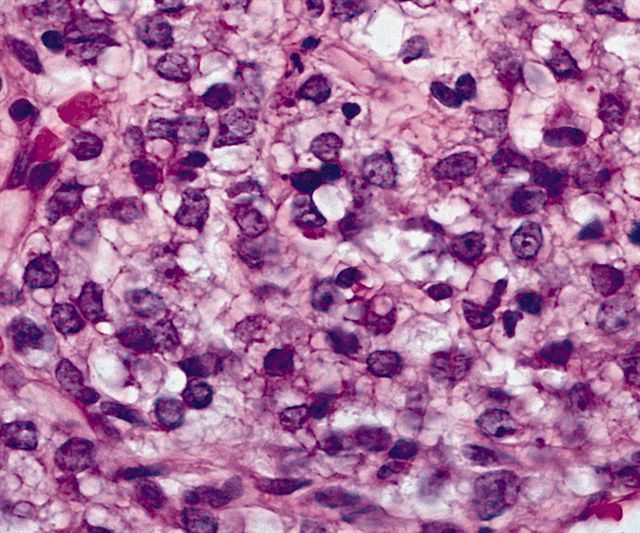

- High grade

- Hypercellular solid sheets of back to back cells with round cell or primitive cytomorphology in > 5% of the sampled tumor

- Cells can have a small amount of hypereosinophilic cytoplasm, a finding of no clinical significance but of significant diagnostic confusion, especially in a limited sample

- Pitfalls and tips

- High grade tumors are so cellular that you can typically walk across nuclei in a high power field without stepping in matrix

- When in doubt, especially in a small sample, pursue molecular testing (typically fluorescent in situ hybridization) for FUS gene rearrangement

- If no FUS gene rearrangement is detected and your suspicion is high that the lesion represents myxoid liposarcoma, proceed to EWSR1 fusion testing, as EWSR1::DDIT3 fusions are detected in rare cases (see Molecular / cytogenetics description)